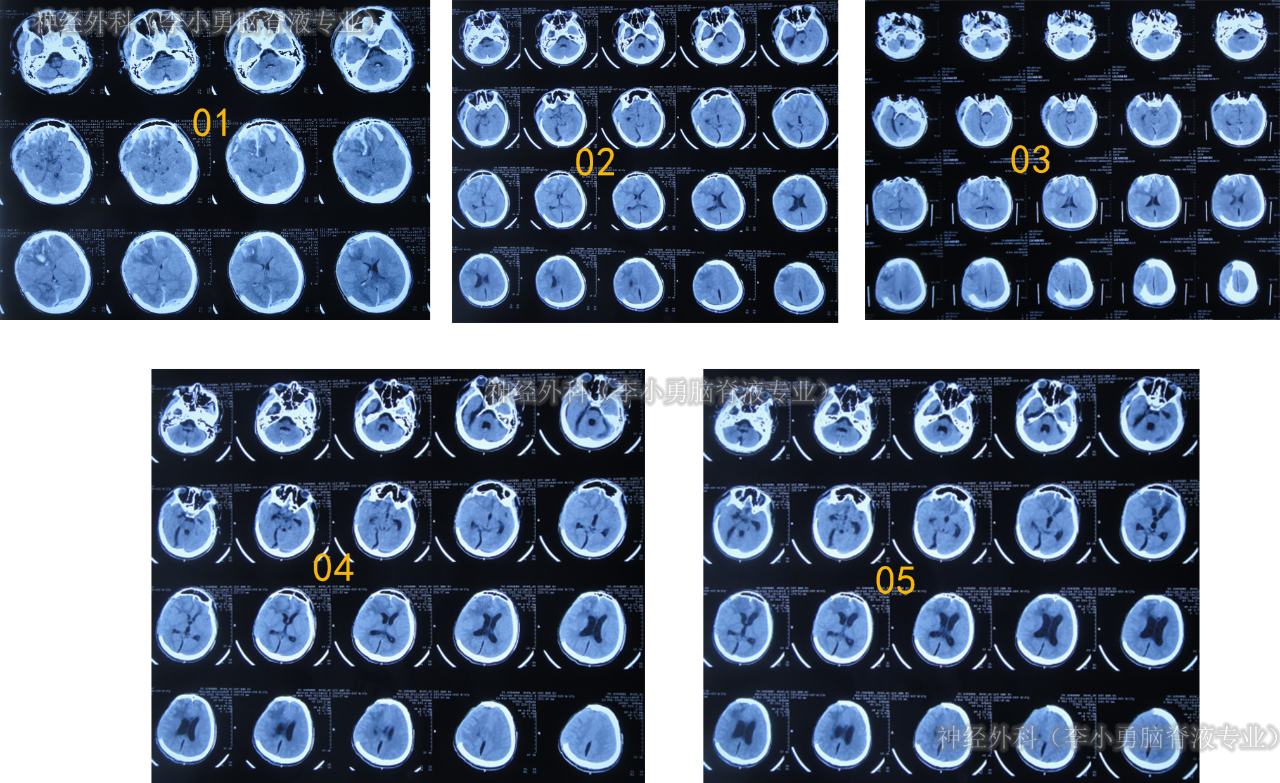

患者于2022年2月2日,不慎摔倒头部磕到地面,当时呈嗜睡状态,呕吐1次,大小便失禁,由120急送至当地县某医院,查头颅CT示右额部血肿(片子丢失),当即转至上级的河北省唐山市某医院,查头颅CT示右额部血肿、脑疝(图-1);检查期间出现昏迷、呕吐、四肢强直。

图-1:2022年2月2日头颅CT

急诊当天进行了去骨瓣减压+血肿清除术(图-2)。

图-2:2022年2月2日术后头颅CT

去骨瓣减压+血肿清除术后第2天即2022年2月3日,头颅CT示出血有增多(图-3)。

图-3:2022年2月3日头颅CT

术后3天即2022年2月4日,患者苏醒,能言语,但遗留左侧肢体不能活动,低钠血症,查头颅CT示仍有较多积血(图-4)。

图-4:2022年2月4日头颅CT

继续治疗1月期间出现数次呕吐,行胃肠镜检查未见异常(片子丢失),给予胃管及肠管置管,期间5次查头颅CT(图-5)均示脑室逐渐出现扩张,并加重。

图-5:5次查头颅CT